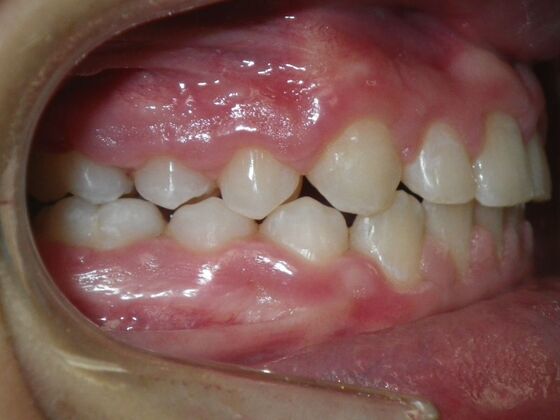

Orthodontic treatment in Phases: Case 8

Description

Dylan presented with a functional crossbite in which we used removable expansion appliances for 12 months, followed by bracketing of upper and lower teeth including primary ones to gain alittle more expansion, allowed to wear retainers for 6 months and then followed closely with 6 month ortho recalls and began Phase 2 treatment within 24 months and finished his ortho treatment.